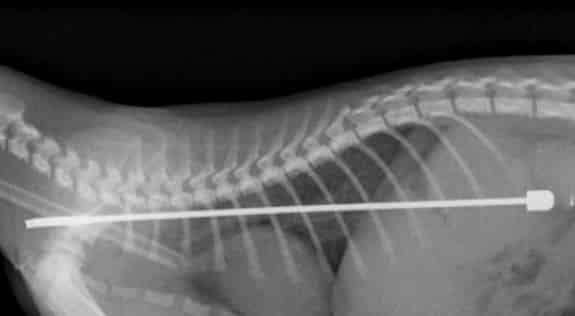

gato-engole-antena02